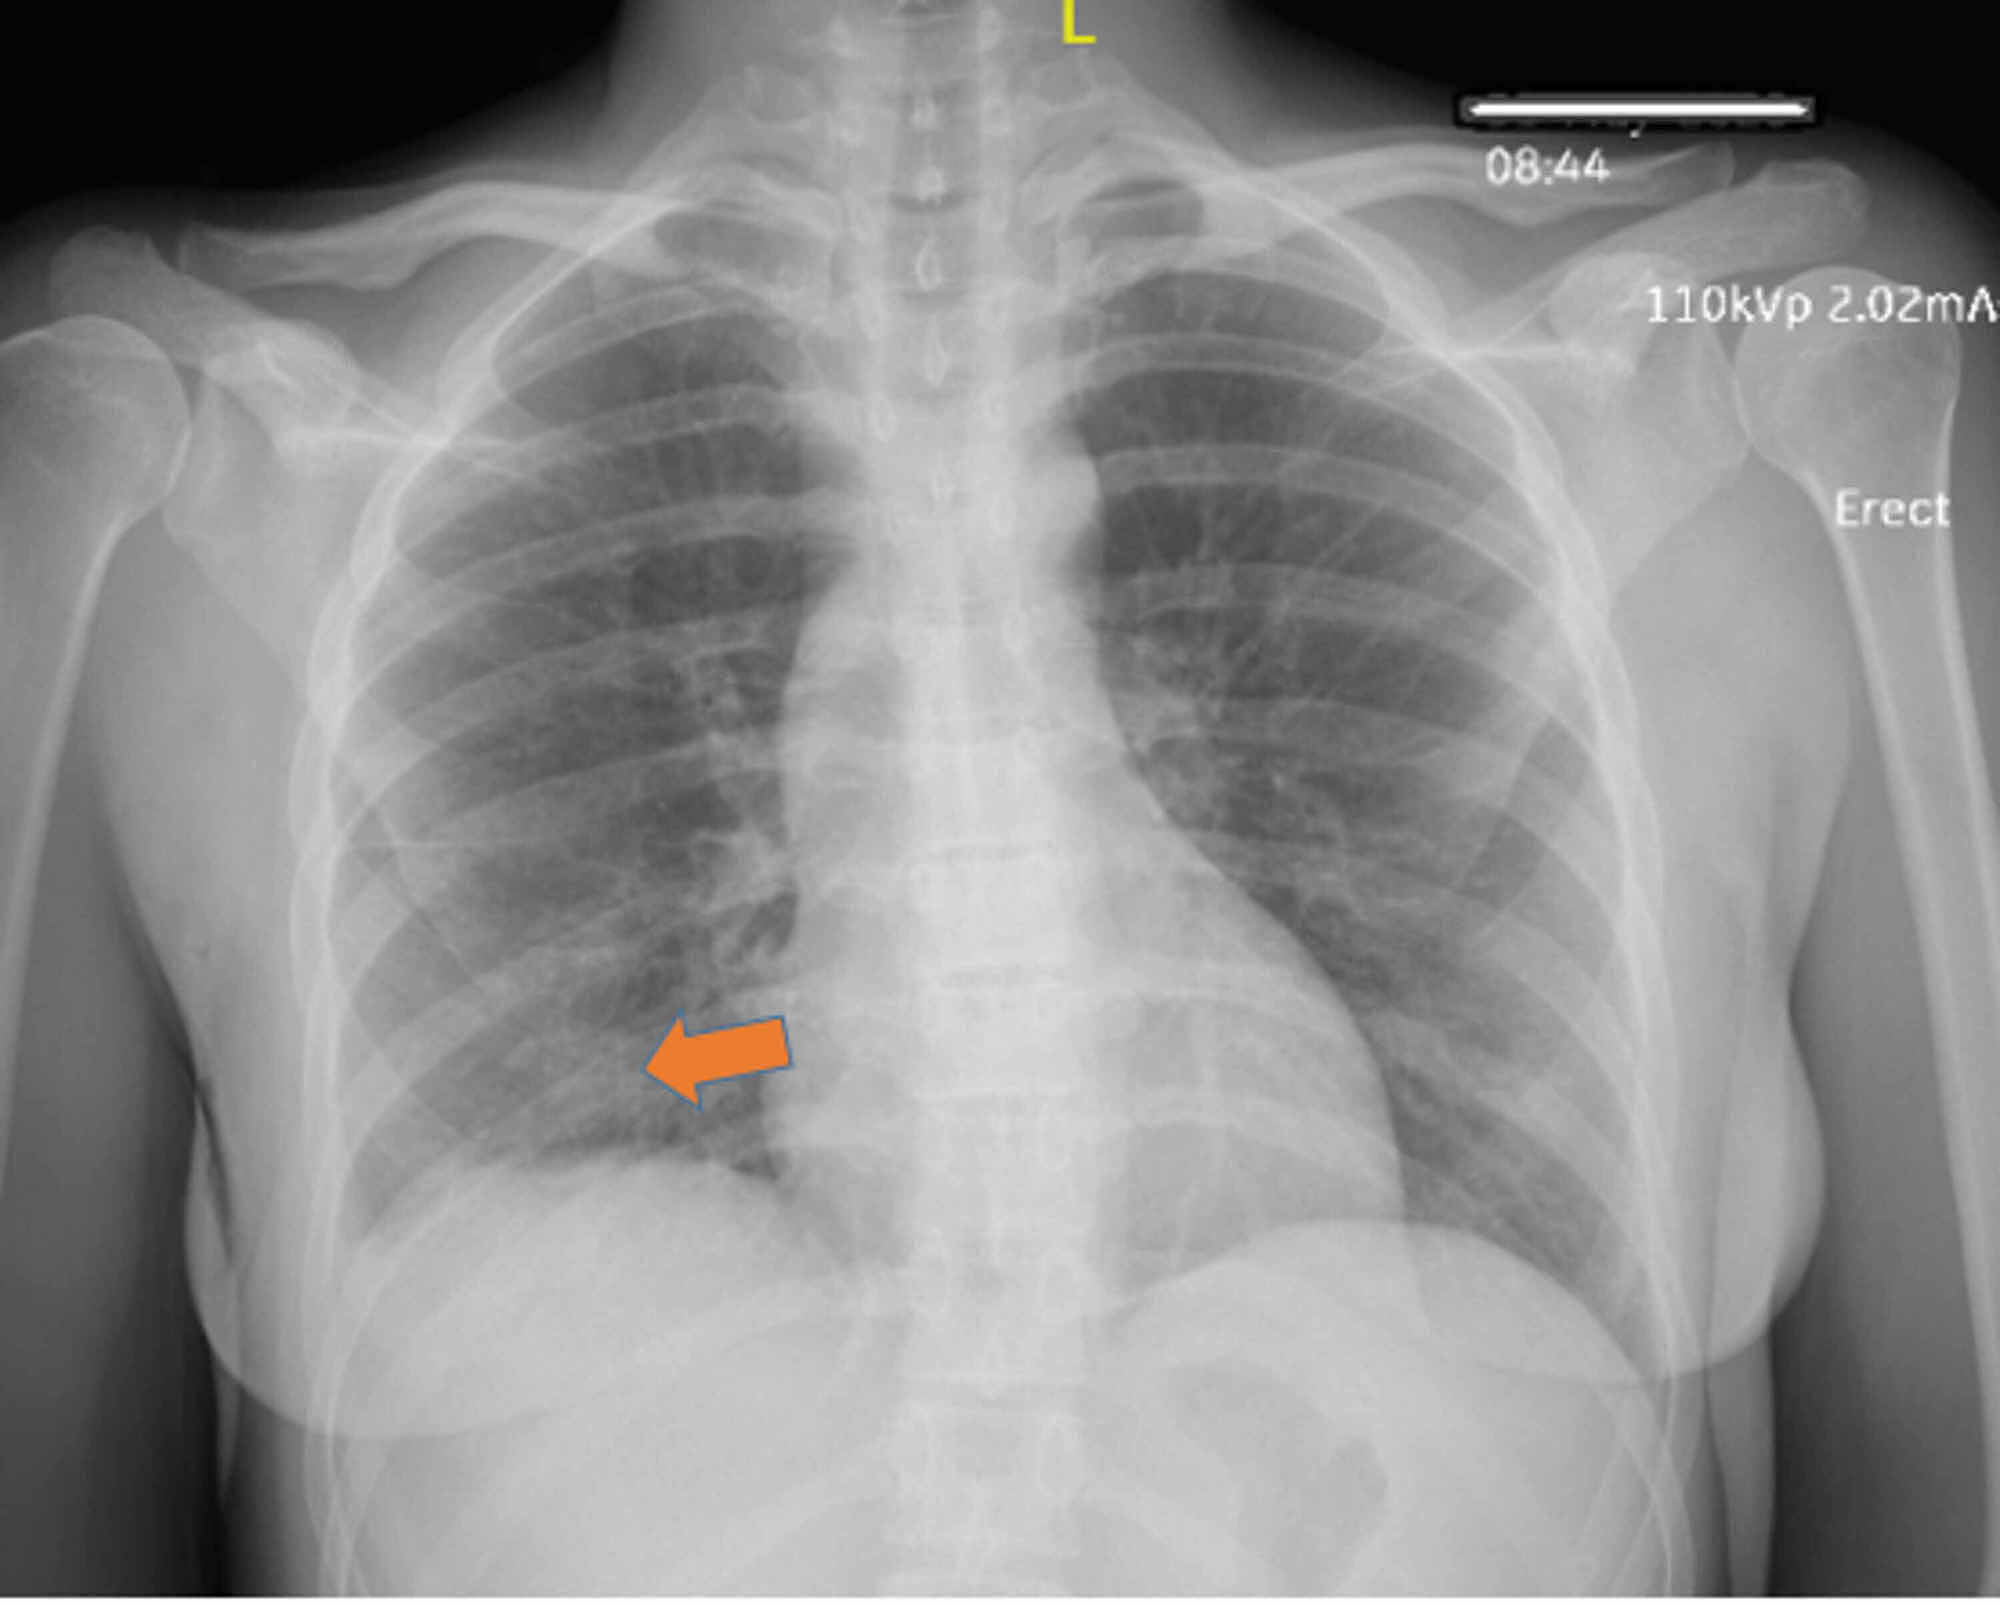

Chest X Ray In The Covid 19 Pandemic Radiologists Real World Reader Performance European Journal Of Radiology

Chest X Ray Severity Score In Covid 19 Patients On Emergency Department Admission A Two Centre Study European Radiology Experimental Full Text